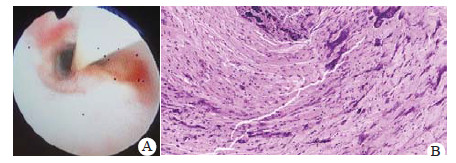

1 资料与方法病例1, 患儿, 女, 1岁8个月, 因“咳嗽发热2 d, 气促声嘶1 d”于2017年2月10日入院。既往体健。入院查体:T 37.5 ℃, P 160次/min, R 38次/min, BP 128/78 mmHg(1 mmHg=0.133 kPa), 神志欠清, 呼吸促, 三凹征明显, 双肺呼吸音粗, 偏低, 未闻及明显干湿啰音, 心音中, 腹软。立即予气管插管呼吸机辅助通气, 呼吸机显示气道峰压高, 经气管插管吸出褐色黏性物质后气道峰压下降。之后行纤维支气管镜检查, 镜下见气管支气管黏膜红肿, 并可见大量黏液条索状物质(图 1A), 予冲洗清除完毕后送检病理, 提示(支气管)小片炎性坏死组织(图 1B)。诊断:急性假膜性坏死性喉气管支气管炎。患儿入院后查血常规提示白细胞计数14.11×109/L, 中性粒细胞85.8%, 超敏C反应蛋白63 mg/L, 痰培养提示甲氧西林敏感金黄色葡萄球菌, 痰呼吸道病毒检测阴性, 胸部CT提示肺炎, 左下肺为著, 右侧胸膜反应, 气管上段线样稍高密度影(图 1C)。入院后予气管插管呼吸机辅助通气2 d, 吸痰清理呼吸道, 美罗培南抗感染, 甲泼尼龙抗炎等治疗, 患儿病情逐渐缓解。入院5 d拍背后剧烈咳嗽, 随即出现发绀, 心搏呼吸骤停, 立即心肺复苏2 h无效, 予以建立体外膜肺支持, 但最终因多器官功能障碍综合征宣告死亡。

| 图 1 A:病例1纤支镜下见气管黏膜红肿, 并可见黏液条索状物质; B:病理结果(支气管)小片炎性坏死组织(HE, 200×); C:胸部CT提示气管上段线样稍高密度影 |